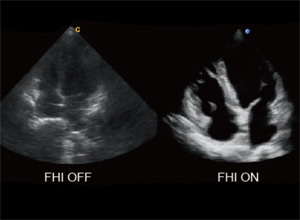

- FHI фазоинверсная тканевая гармоника

Тканевая гармоника

Тканевая гармоника нового поколения с фазовым сдвигом существенно улучшает качество визуализации в В-режиме, особенно для сложных пациентов и поддерживается на всех датчиках. До 5 переключаемых рабочих частот.